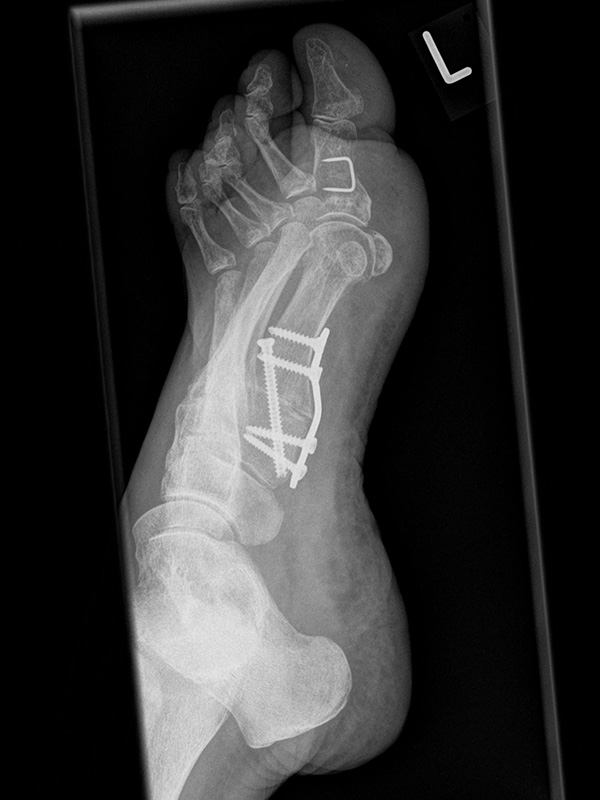

Fuß in 45° Supination ohne Belastung

Positionierung:

• Der Patient sitzt auf dem Untersuchungstisch.

• Der Fuß steht auf der Kassette, der mediale Fußrand wird um 45° angehoben (optional Verwendung eines Keilkissens).

• Der Zentralstrahl wird auf das Os naviculare ausgerichtet.

• Die Röhre ist 0° vertikal ausgerichtet.

Kennzeichen des Röntgenbildes:

• Gute Einsicht in das Tarsometatarsale I Gelenk.

Besondere Bemerkungen zum Beispielbild:

• Die 45° Supinationsaufnahme wird häufig eingesetzt, um die knöcherne Konsolidierung einer Lapidus-Arthrodese zu beurteilen.

• Hier das Beispiel 6 Wochen postoperativ nach Tarsometatarsale I Fusion mit Stabilisierung durch eine plantare Platte.

• Die Arthrodese zeigt sich weitgehend überbaut bei korrekter Lage des Osteosynthesematerials.

Zur Vollansicht und zum Lesen der Bildbeschreibung bitte die Bilder anklicken.